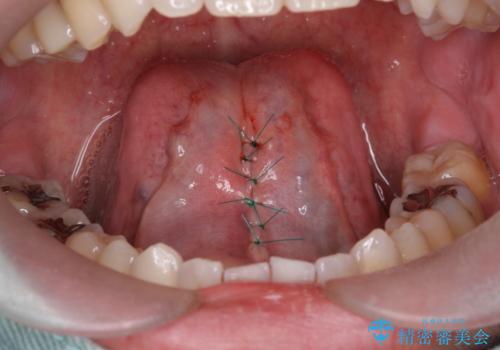

- 舌を動かしにくいとのことで来院されました。

舌の裏側にある舌小帯という部分が短い状態だったため、舌小帯の切除をすることとなりました。

術後の治りも良く、以前よりも話しやすくなったと大変喜んでいただけました。